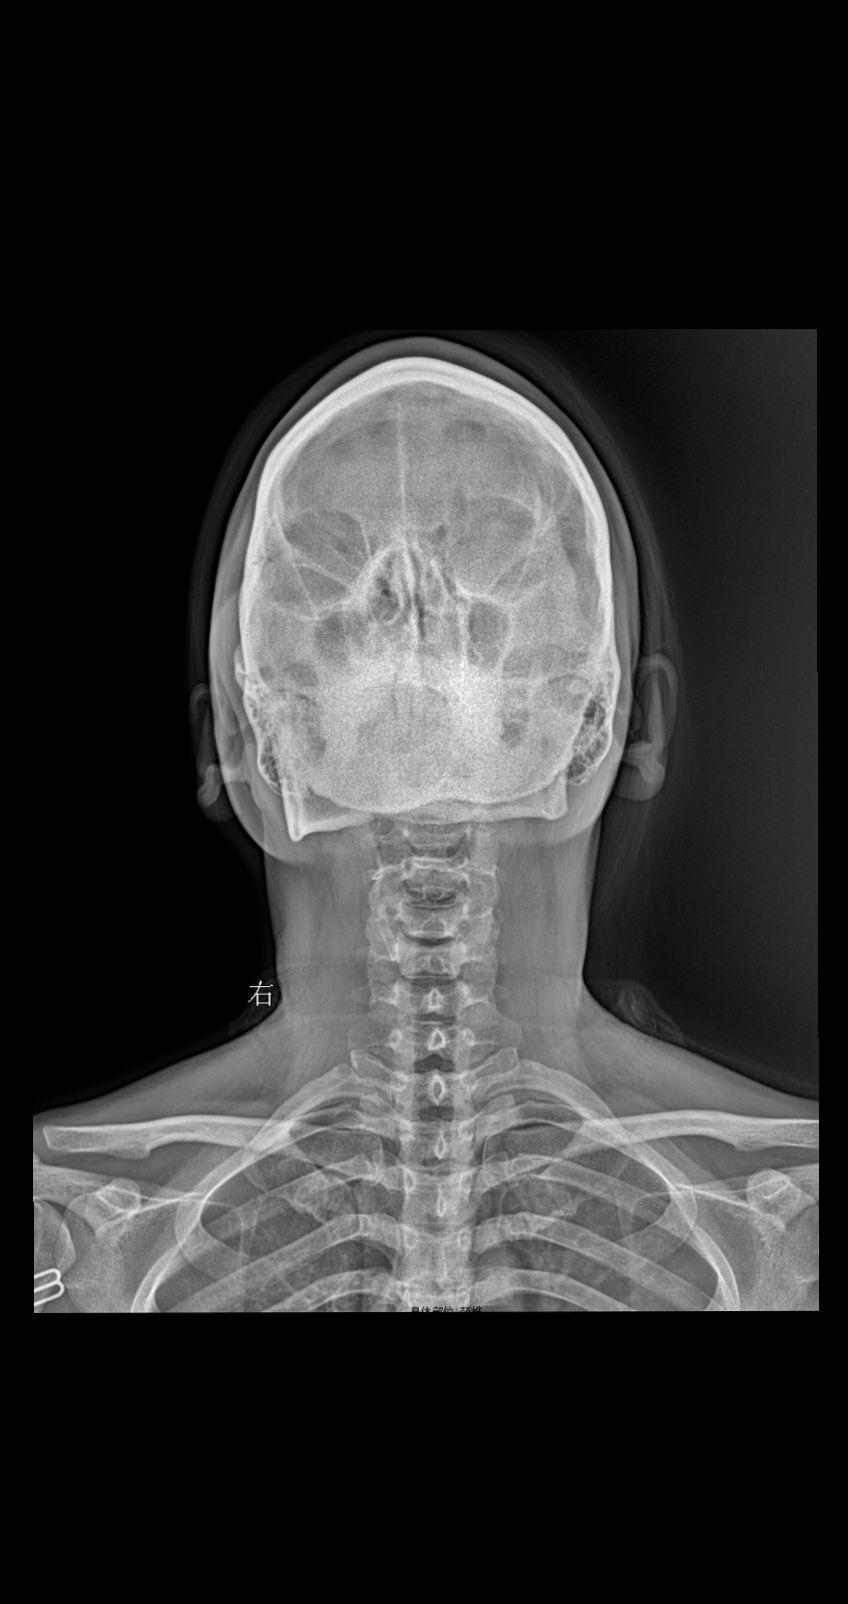

男34 腰椎疼痛 颈椎正侧+腰椎正侧